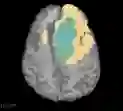

Deep neural network models used for medical image segmentation are large because they are trained with high-resolution three-dimensional (3D) images. Graphics processing units (GPUs) are widely used to accelerate the trainings. However, the memory on a GPU is not large enough to train the models. A popular approach to tackling this problem is patch-based method, which divides a large image into small patches and trains the models with these small patches. However, this method would degrade the segmentation quality if a target object spans multiple patches. In this paper, we propose a novel approach for 3D medical image segmentation that utilizes the data-swapping, which swaps out intermediate data from GPU memory to CPU memory to enlarge the effective GPU memory size, for training high-resolution 3D medical images without patching. We carefully tuned parameters in the data-swapping method to obtain the best training performance for 3D U-Net, a widely used deep neural network model for medical image segmentation. We applied our tuning to train 3D U-Net with full-size images of 192 x 192 x 192 voxels in brain tumor dataset. As a result, communication overhead, which is the most important issue, was reduced by 17.1%. Compared with the patch-based method for patches of 128 x 128 x 128 voxels, our training for full-size images achieved improvement on the mean Dice score by 4.48% and 5.32 % for detecting whole tumor sub-region and tumor core sub-region, respectively. The total training time was reduced from 164 hours to 47 hours, resulting in 3.53 times of acceleration.